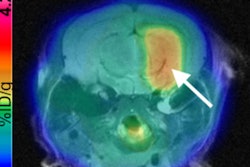

The combination of machine learning and radiomics can predict the molecular subtypes of medulloblastoma, paving the way for early diagnosis and better treatment of this common cancerous pediatric brain tumor, according to research presented last week at the American Medical Informatics Association (AMIA) meeting in San Francisco.

Researchers from Stanford University and Harvard University have trained and tested a machine-learning model that was able to predict medulloblastoma subtypes based on image textures extracted from brain MR images. By identifying these subtypes sooner, clinicians could then quickly decide on the therapeutic approach that's best for the particular subtype, according to the authors.

After three board-certified radiologists manually annotated the tumor boundaries, 590 MRI-based radiomic features were extracted from both the T1- and T2-weighted imaging data. These features included the peak position of maximal intensity, entropy of histograms, histogram bin features, histogram statistical features, local area integral invariant features, tumor edge sharpness features, Daube features on the histogram, and Gabor wavelet features.